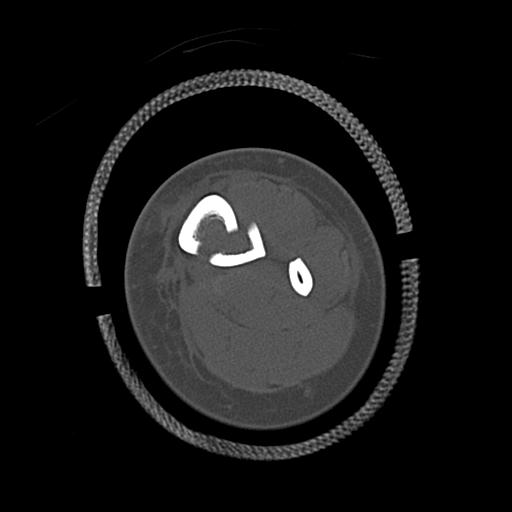

102803 1/12(キウスなし) 1/27 左下腿 4R 30歳女性 左脛骨軸内釘